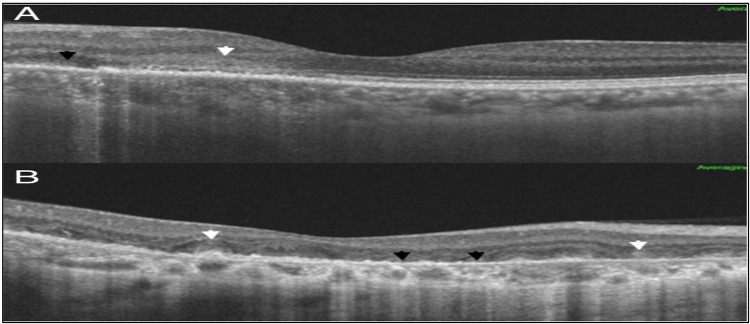

Case presentation: A 42 year old woman with steadily declining vision in her right eye for the previous four months presented to the emergency department. On the Snellen chart, the best-corrected visual acuity was 20/28 in the left eye and 20/100 in the right eye. The intraocular pressure (IOP) of the right and left eyes was 15 and 16 mmHg, respectively. Anterior segment examination was unremarkable. Fundus examination of the right eye revealed a gray finger-like lesion with an active border. The left eye showed a small yellowish-finger-like lesion involving the nasal macula. Disruption in the ellipsoid zone in the right eye and the parafoveal region in the left eye was demonstrated using optical coherence tomography (OCT). Fundus fluorescein angiography revealed bilateral, finger-like branching lesions were seen on fundus fluorescein angiography (FFA). Fundus Autofluorescence (FAF) showed hypoautofluorescence lesions with hyper-autofluorescence edges. Both eyes were diagnosed with active serpiginous choroiditis, after excluding any active infections through blood work-up. The patient was started oral prednisolone 0.5 mg/kg tapering; however, because the patient would be traveling for three weeks, the systemic oral steroid with an intravitreal dexamethasone implant in each eye. After nine days, there was noticeable improvement in the visual acuity of the right eye with normal intraocular pressure. OCT showed minimal restoration of the ellipsoid zone in the right eye, with resolved inflammatory material in both eyes (Figure 1). After starting Azathioprine, disease activity was suppressed for six months without relapsing.